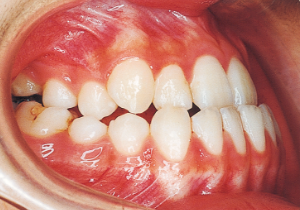

2 After Phase 2 Treatment 5-9-’92

Aware that treatment would be challenging, we proceeded with the first phase of treatment based on the current functional status and anticipated developmental implications (7). During the mixed dentition phase, the body responds readily to treatment, allowing for relatively rapid tooth movement and changes in jaw position (8,9). Subsequently, once freed from mechanical stimulation, growth continues according to inherent predispositions, often appearing to disregard occlusal functional efficiency (10,11). These changes are clearly observable on cephalometric radiographs (12). After confirming the extent and direction of growth, we decided to incorporate surgical intervention into the treatment plan and wait until the age when growth begin to decline.

Afterwards, follow-up was conducted, but based on the growth pattern, surgical intervention was determined necessary, and the patient entered a period of regular observation.